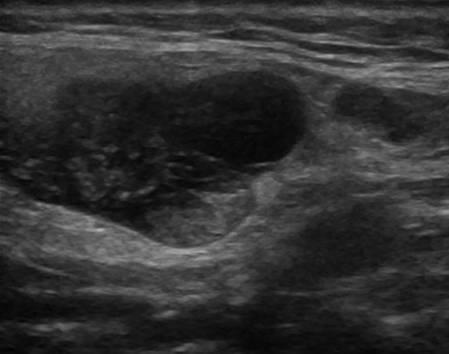

U tuyến nước bọt

U tuyến nước bọt - Ảnh 2

U tuyến nước bọt - Ảnh 3

U tuyến nước bọt - Ảnh 4

» Thông tin: Nam giới – 71 tuổi.

» Lâm sàng: Khối vùng mang tai.

# U lympho tuyến nang (U Warthin) tuyến nước bọt mang tai.